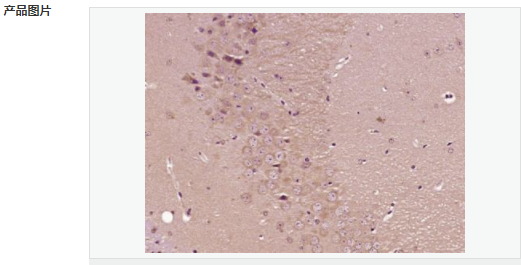

交叉反應(yīng):Mouse,Rat(predicted:Human,Pig) 推薦應(yīng)用:IHC-P,IHC-F,IF,ELISA

產(chǎn)品應(yīng)用ELISA=1:5000-10000 IHC-P=1:100-500 IHC-F=1:100-500 IF=1:100-500 (石蠟切片需做抗原修復(fù))

FSCN1為細(xì)胞骨架肌動(dòng)蛋白的一種,該蛋白有蛋白結(jié)合,橋連、肌動(dòng)蛋白絲結(jié)合的功能。 主要參與細(xì)胞增殖、肌動(dòng)蛋白細(xì)胞骨架組織和生物發(fā)生、肌動(dòng)蛋白絲束形成。Fascin也是一種actin結(jié)合蛋白,它的功能是把F-actin聚集捆綁成束,與細(xì)胞的運(yùn)動(dòng)相關(guān)。病理情況下,各種惡性腫瘤細(xì)胞經(jīng)常高表達(dá)Fascin。